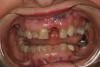

Fig 6. Deep bite, excessive wear, and missing No. 9 present a challenging case for restorative rehabilitation.

Figure 6